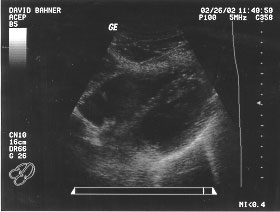

Splenorenal (unlabeled)